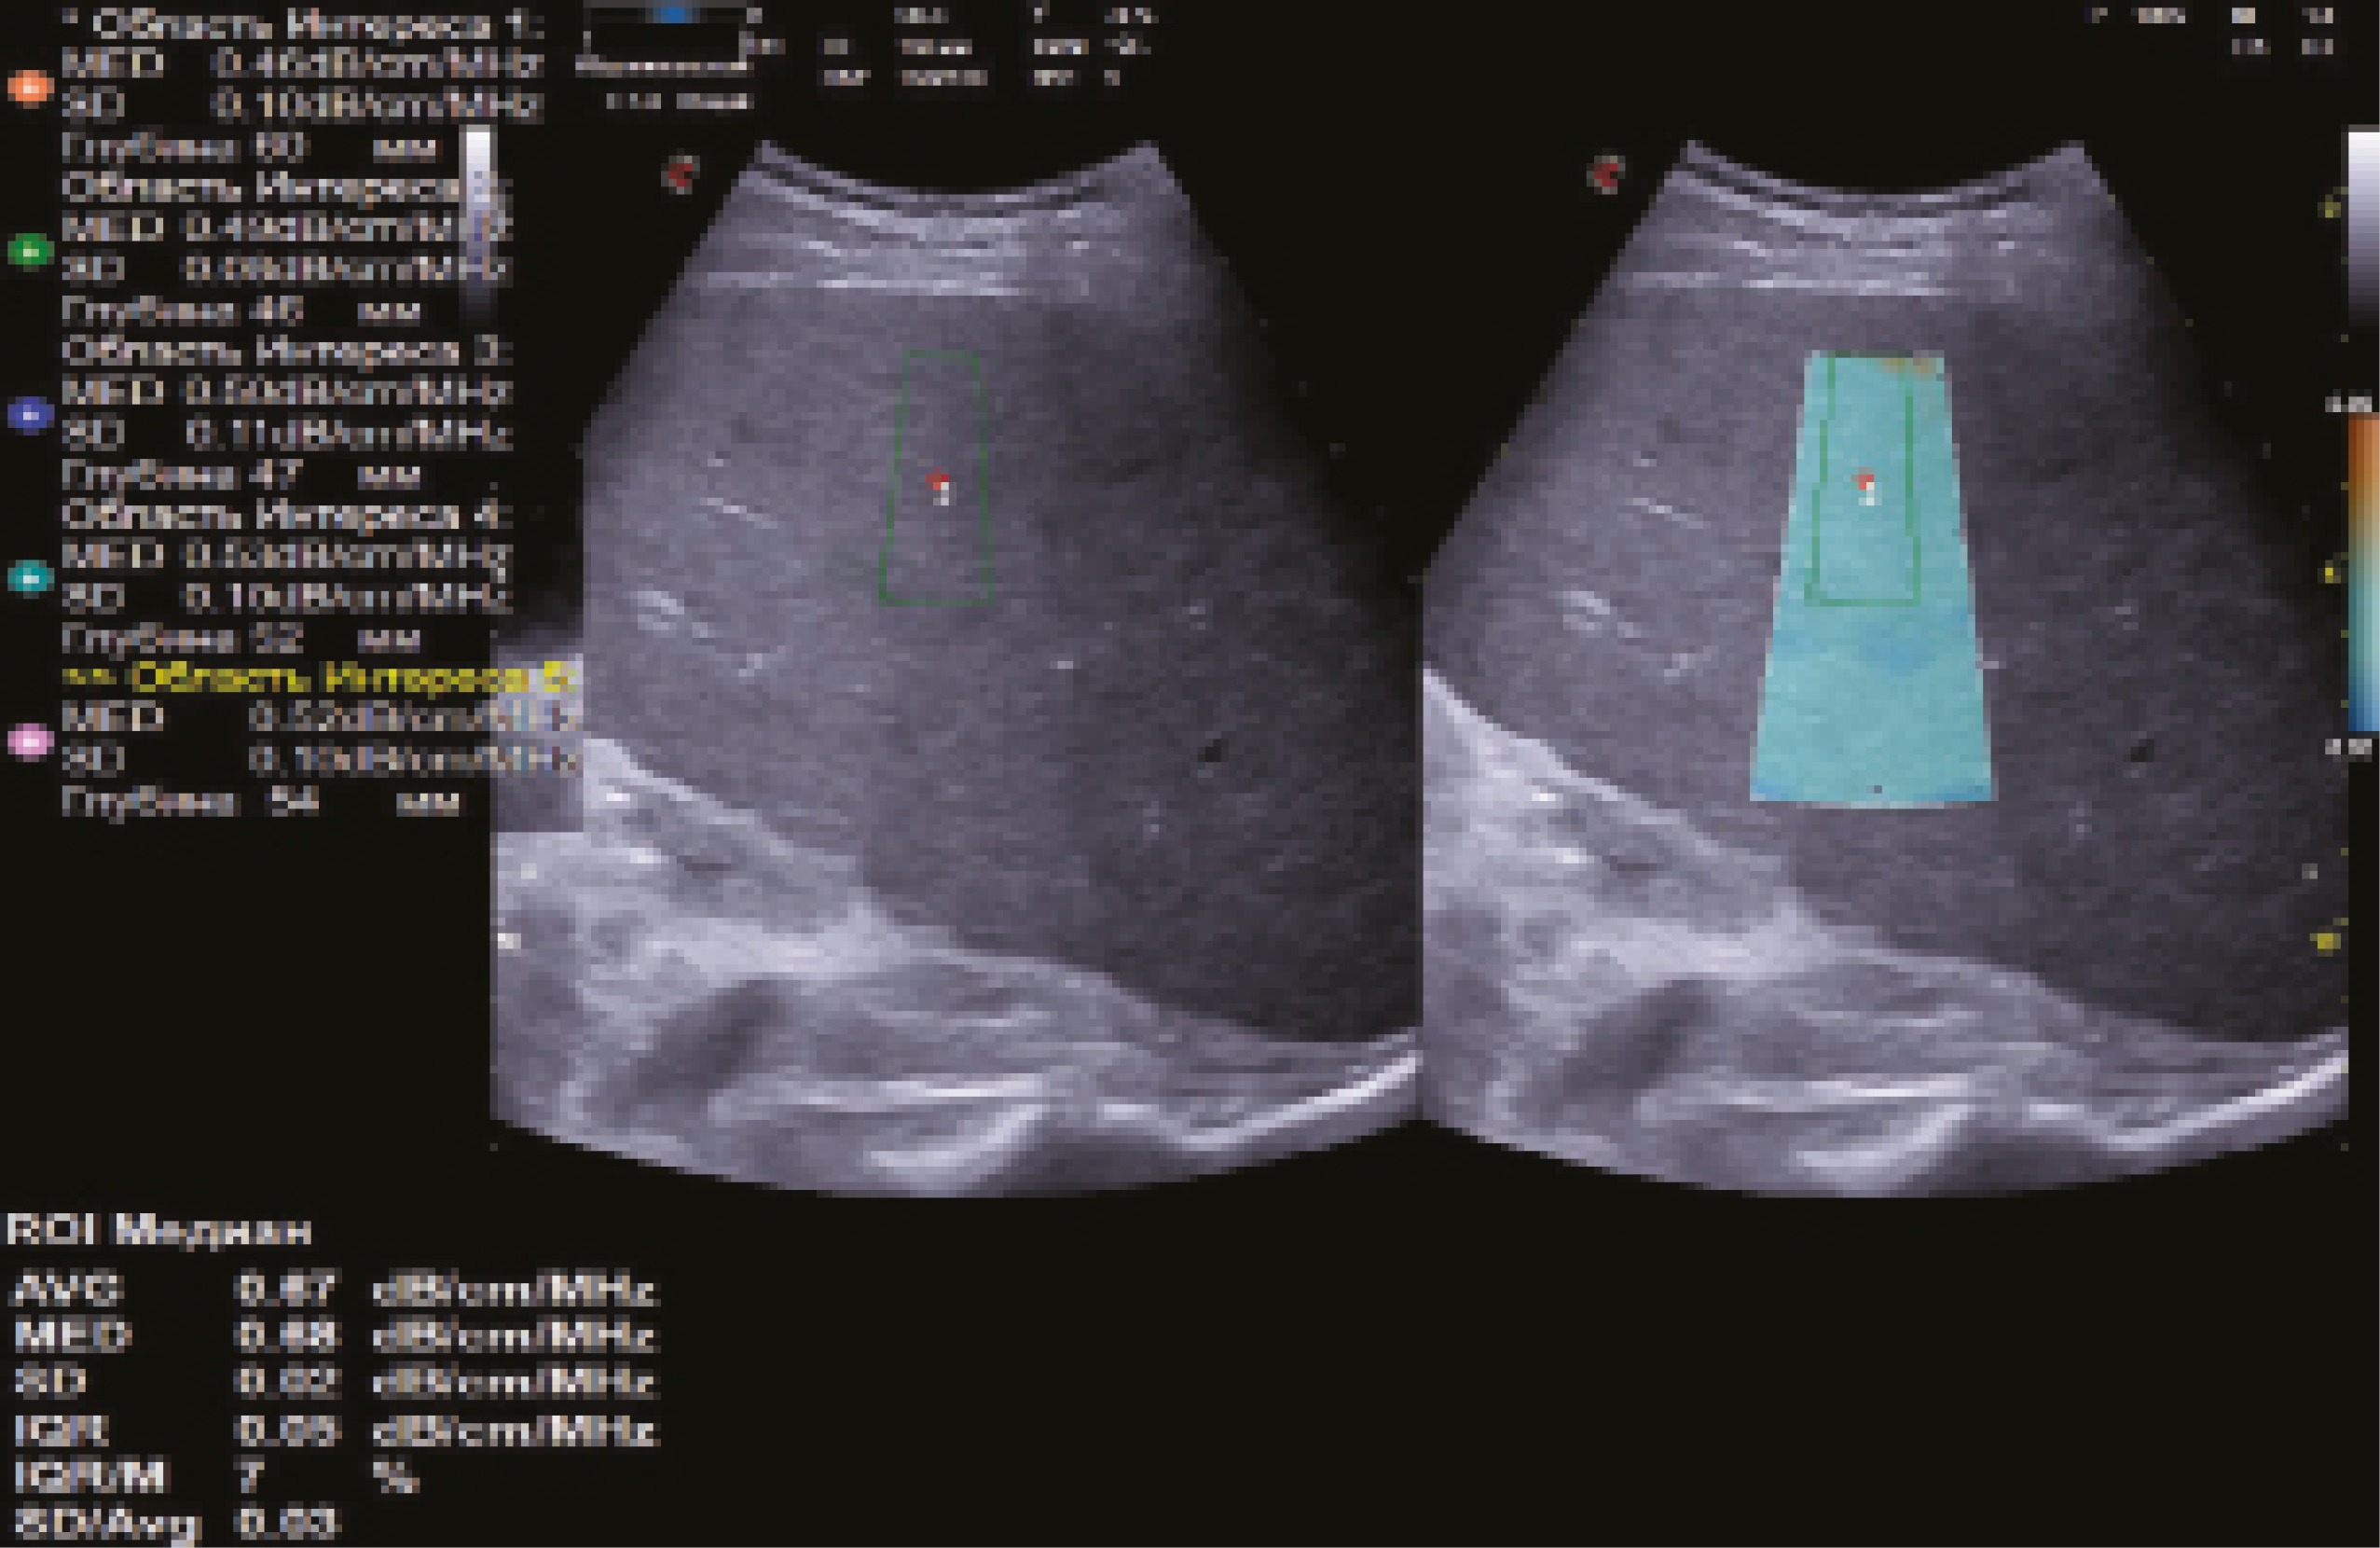

На основании анализа действующих зарубежных и отечественных клинических рекомендаций, касающихся количественной оценки различных клинико-морфологических форм диффузных изменений печени (преимущественно фиброза)1 [12–16], и результатов собственных исследований [17–21] нами предложены следующие правила проведения количественной УЗ-стеатометрии печени у пациентов с подозрением на стеатоз печени (рис. 9):

- использовать при наличии возможность сопоставления двух окон с единой визуализацией печени в В-режиме и в режиме количественной стеатометрии для дополнительного контроля;

- коррекция размера РИ: средняя ширина – 10–15 мм, большая длина – более 25 мм (для стандартизированной оценки коэффициента затухания УЗ-волны с вовлечением максимального объема ткани печени по глубине), не доходя нижней границей РИ до диафрагмы (оптимальная площадь РИ – 5–6 см2);

- центральное расположение РИ параллельно капсуле печени, на глубине не менее 10 мм (фиксация верхней границы РИ), под прямым углом к УЗ-лучам для минимизации количества артефактов;

- расположение РИ вдали от соседних органов и/или структур;

- в случае наличия у разных моделей УЗ-обо-рудования первого большого и второго малого проверочного РИ рекомендовано расположение первого РИ по правилу 5, второго РИ – внутри первого РИ по правилу 7;

- определение среднего значения коэффициента затухания УЗ-волны по данным не менее 5 измерений;

- отношение интерквартильного размаха (IQR, interquartile range) к медиане (M, median) не более 30%.

Рис. 9. Эхограмма количественной ультразвуковой стеатометрии печени с определением коэффициента затухания ультразвуковой волны (0,67 дБ/см/МГц, стеатоз печени S1 – минимально выраженный), выполненная по правилам, предложенным авторами